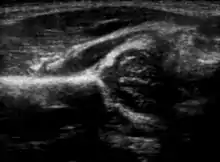

Hip ultrasound

Hip dysplasia diagnosed by ultrasound[40] and projectional radiography ("X-ray").[41] Ultrasound imaging is generally preferred at up to 4 months due to limited ossification of the skeleton.[39][notes 1]